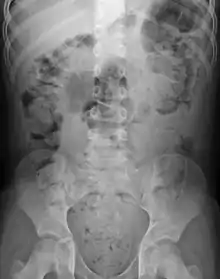

Constipation in a young child seen on X-ray. Circles represent areas of fecal matter (stool is white surrounded by black bowel gas).

Significant constipation in the plain X-ray of an 8-year-old

Abdominal X-rays are generally only performed if bowel obstruction is suspected, may reveal extensive impacted fecal matter in the colon, and may confirm or rule out other causes of similar symptoms.[25][17]